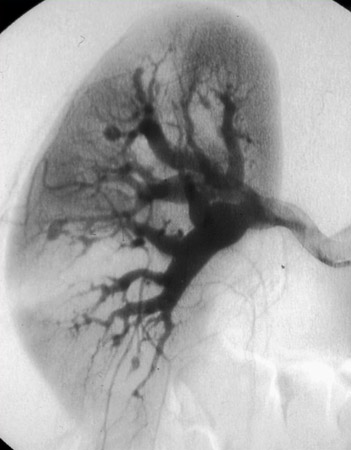

A angiografia convencional é a modalidade de exame de imagem de escolha e deve ser realizada caso haja suspeita clínica de PAN. A sensibilidade relatada é de 89%. A especificidade é de 90% quando realizada em pacientes com suspeita de vasculite.[40] Achados clássicos incluem pequenos aneurismas múltiplos, ectasia vascular e lesões oclusivas focais em vasos de tamanho médio, mais tipicamente nas artérias renais e mesentéricas.

RM ou angiotomografia são alternativas menos invasivas à angiografia convencional, mas são muito menos sensíveis em mostrar microaneurismas.[41] Elas apresentam a vantagem de mostrar áreas de infarto renal e outra patologia potencial. No contexto de alta suspeita de PAN com tomografia computadorizada (TC) ou angiografia por ressonância magnética normal, ainda é necessário realizar uma angiografia convencional.

A PAN não afeta os pulmões, mas a radiografia torácica pode ser útil em descartar outras doenças, como outras vasculites que podem afetar os pulmões, e excluir infecção.[Figure caption and citation for the preceding image starts]: Angiografia renal mostrando aneurismas, uma característica clássica de poliarterite nodosa (PAN)Do acervo do Dr Raashid Luqmani [Citation ends].